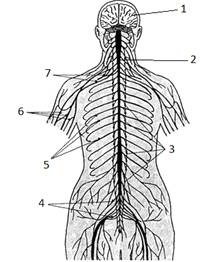

В нервной системе выделяют два основных отдела:

центральную нервную систему – головной (1) и спинной мозг (2) и периферическую

– нервы (5, 6), нервные сплетения (4, 7) и узлы (3).

Деление на центральную и периферическую части

достаточно условно, так как нервная система едина. Более функционально деление

нервной системы на соматический и вегетативный отделы, каждый из которых имеет

центральную и периферическую части. К центральной части соматической нервной

системы относятся структуры головного и спинного мозга, к периферической –

черепно-мозговые и спинномозговые нервы и узлы. Соматический отдел нервной

системы иннервирует тело и некоторые внутренние органы – язык, гортань, глотку,

мышцы глазного яблока, среднего уха.

Вегетативный отдел нервной системы состоит из

симпатической и парасимпатической частей, которые включают скопления клеток,

расположенных в головном и спинном мозге, а также узлы, сплетения и вегетативные

нервы, иннервирующие внутренние органы.

В нервной системе выделяют афферентный и

эфферентный отделы. Первый отдел отвечает за поступление информации в нервную

систему из внешней и внутренней среды, а второй обеспечивает управляющие

воздействия нервной системы на организм.